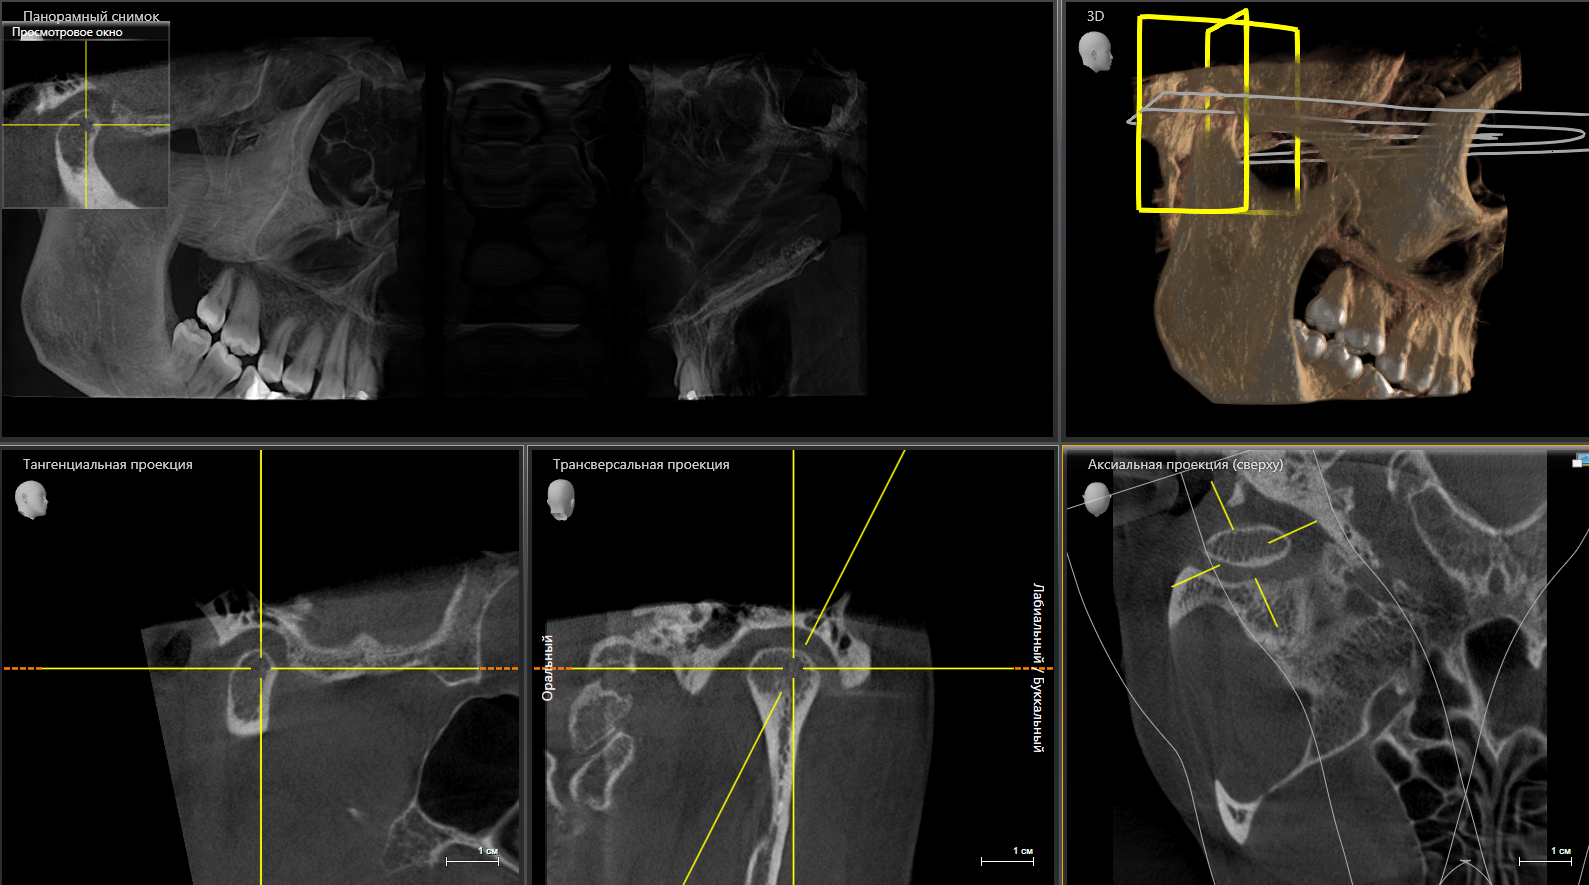

Что вы получаете в итоге? Не просто диск, распечатку или отправку на электронную почту. Вы получаете стопроцентную уверенность. Уверенность в том, что план лечения имплантации составлен идеально, что все каналы будут пройдены до конца, а «зуб мудрости» удалят аккуратно, не задев важные нервы.